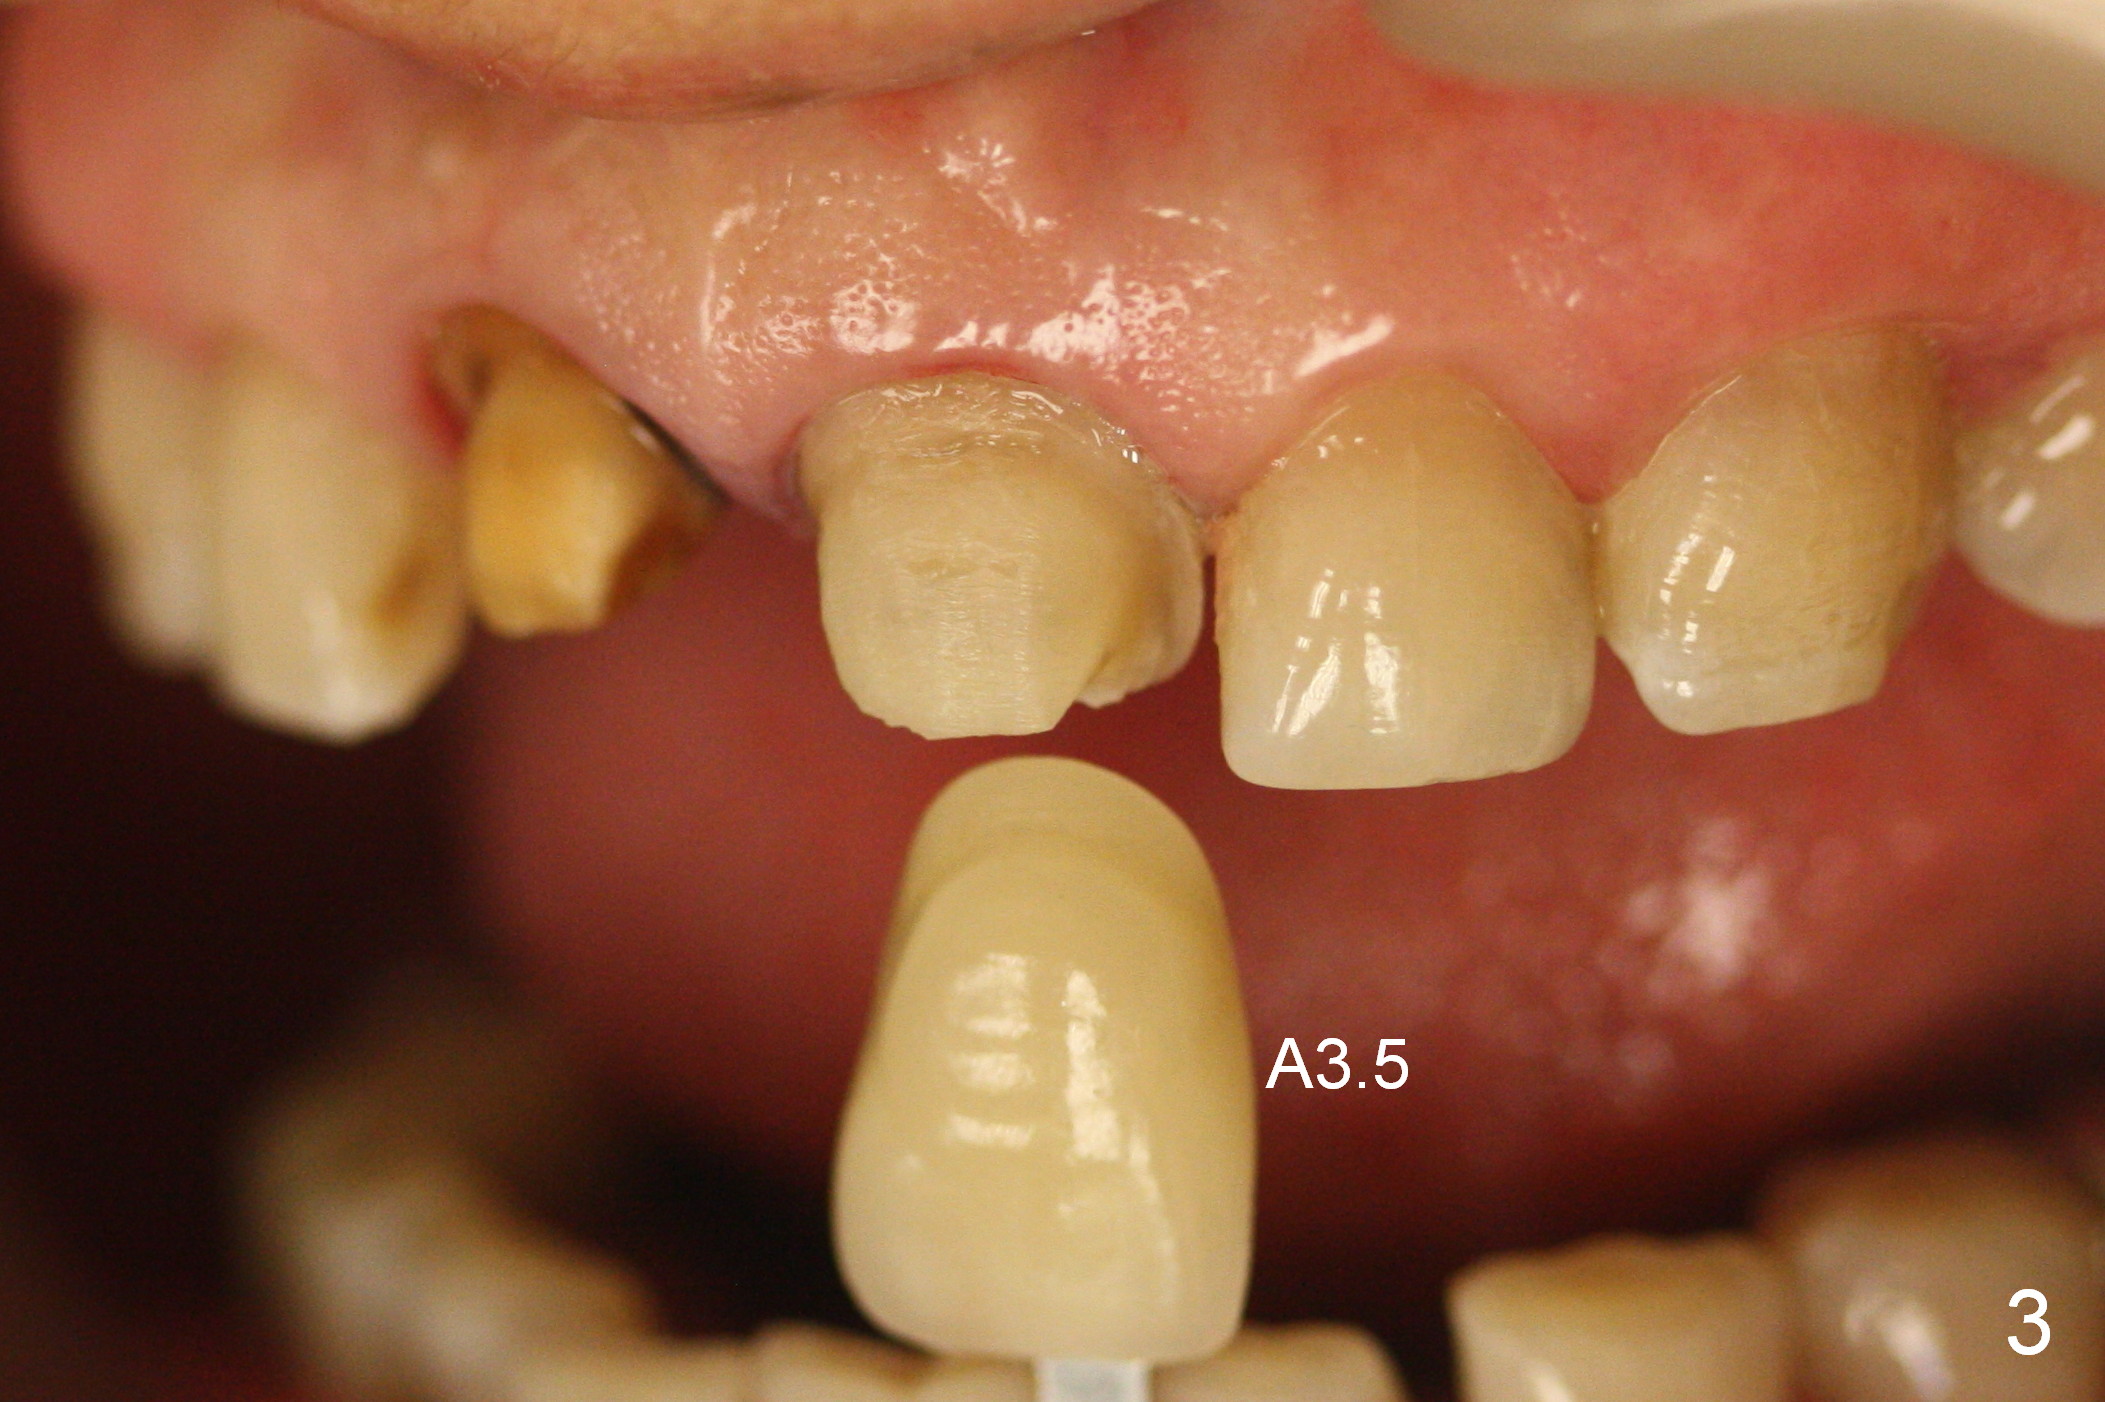

A 54-year-old lady (CL) has a discolored central incisor (#8, Fig.1). Stump shade is shown in Fig.2. Other reference shades are shown in Fig.3-5.